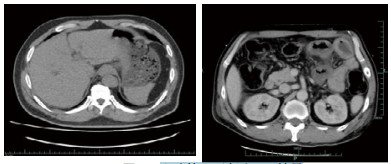

患者,男性,45岁,有长期在老挝居住史,1个月前回本地。因"纳差乏力5 d,少尿伴反应迟钝1 d"入院。否认糖尿病、高血压、腹部外伤及手术病史。有吸食毒品史数年,自行戒毒1个月余。1个月前有牙齿修补术病史,术后曾出现一过性胸闷及乏力感,当时未就诊治疗。5 d前无明确诱因下出现明显纳差乏力,1 d前在外院就诊,查血肌酐正常,未测血糖。近1 d来症状加重,伴尿量减少,反应迟钝,夜间急诊来台州市中心医院就诊。入院查体:体温37.2℃,心率147次/min,呼吸37次/min,血压88/60 mmHg(1 mmHg=0.133 kPa),氧饱和度100%。神志不清,双侧瞳孔直径0.25 cm,对光反射存在,心律齐,未闻及明显杂音,呼吸音清,未闻及啰音,腹平软,无明显压痛及反跳痛,双下肢无水肿,肢端皮温低,四肢存在自主活动,巴氏征阴性。辅助检查:白细胞计数10.5×109/L,中性粒细胞90.7%,血小板计数280×109/L,超敏C反应蛋白134.00 mg/L;血钠157 mmol/L,白蛋白28.4 g/L,淀粉酶290 U/L,全血葡萄糖76.14 mmol/L,血酮体7.6 mmol/L。血清肌酐443 μmol/L,尿素氮26.3 mmol/L;降钙素原33.74 ng/ml;血气分析:氧饱和度96.3%,血乳酸5.5 mmol/L,pH 7.150,PCO2 12.2 mmHg,PO2 111.0 mmHg,实际碳酸氢根4.1 mmol/L,实际剩余碱-24.9 mmol/L。全腹部CT示,肠系膜上静脉及门静脉远端属支多发积气,肠道水肿不明显(图 1)。入院诊断:休克:感染性休克?、糖尿病高渗性昏迷、糖尿病酮症酸中毒、急性肾功能不全、血流感染?

| 图 1 入院时CT检查结果 |